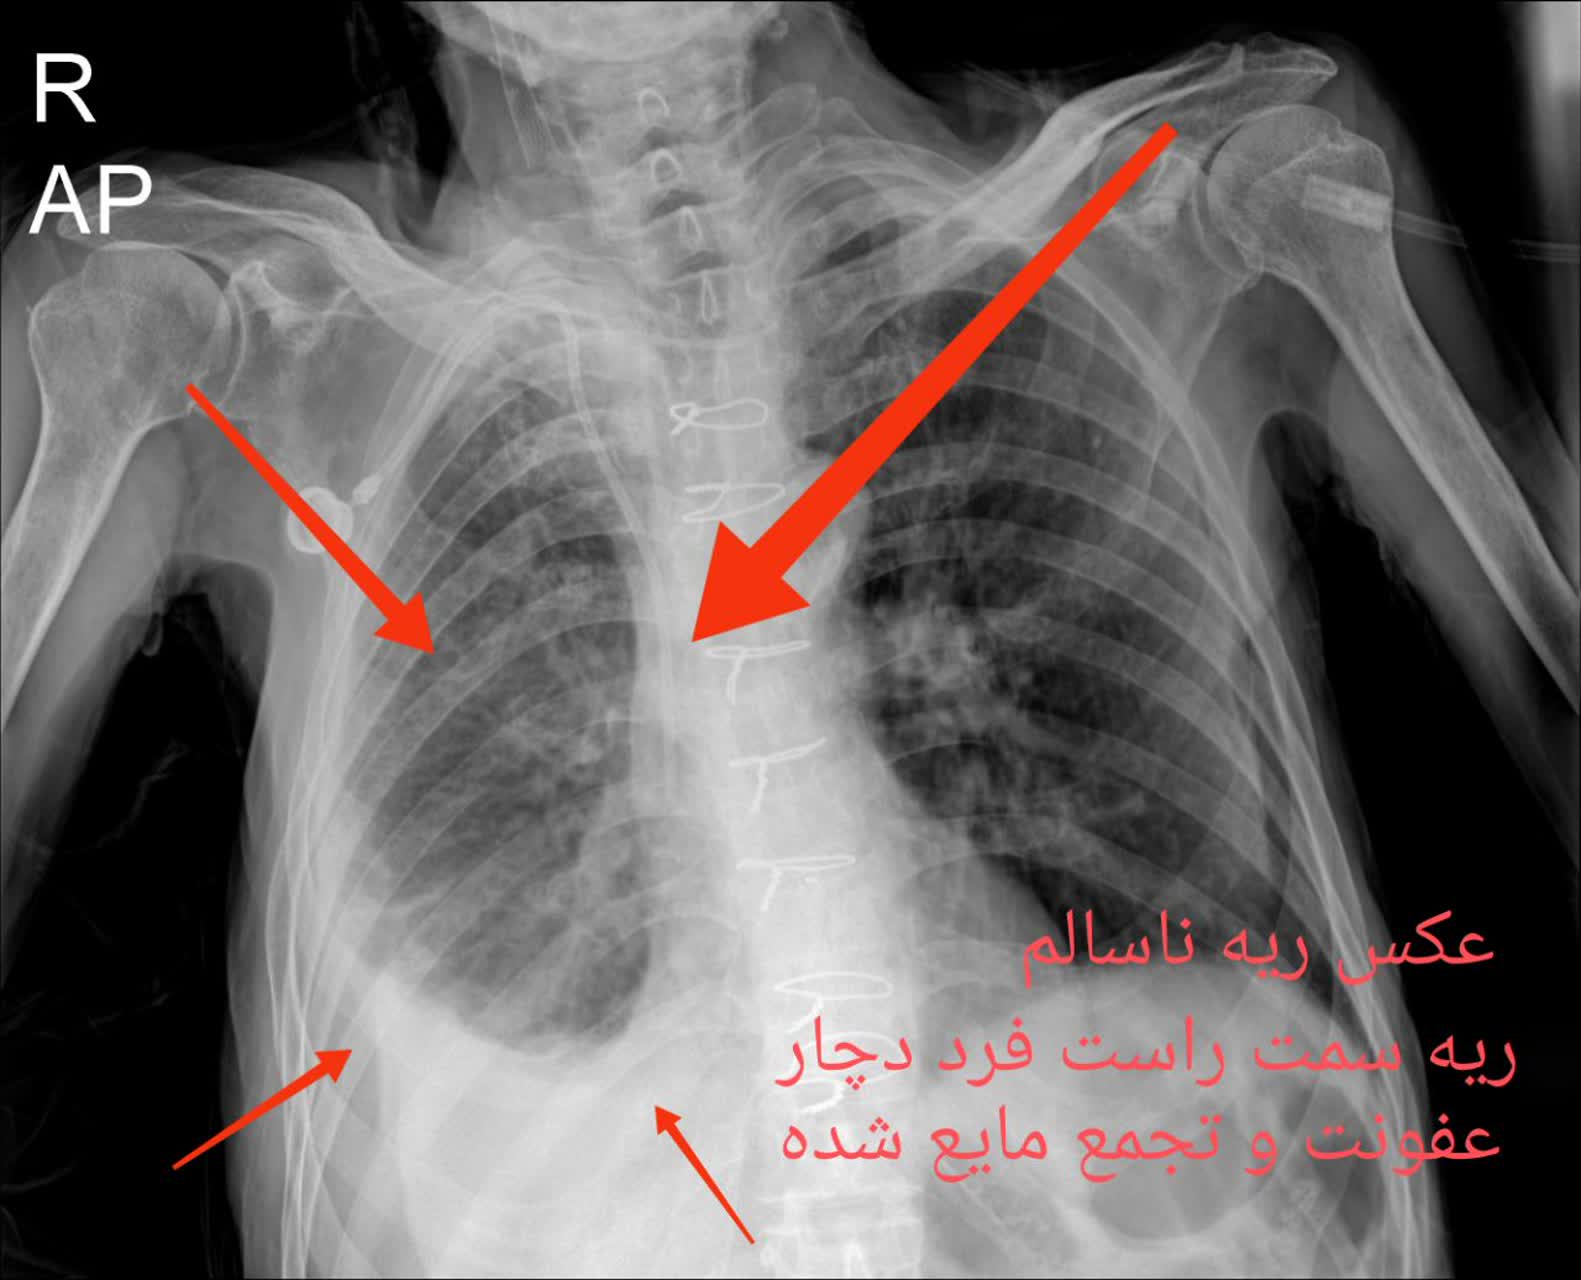

2. التهاب ریه: شامل التهابهای مختلفی از جمله عفونتهای تنفسی و نیز التهاب ریههای مزمن مثل بیماری مزمن انسدادی ریه (COPD) میشود.

5. پنومونی و عفونتهای ریه: عفونتهای باکتریایی یا ویروسی میتوانند به التهاب ریه منجر شوند.

مقایسه عکس ریه سالم و ناسالم

در عکس ریه سالم و ناسالم، تفاوتها معمولاً با چشم غیرمسلح نیز مشهودند. ریه سالم تصویری یکنواخت و شفاف دارد، با خطوط ریوی طبیعی و بدون سایه یا توده. در مقابل، ریه ناسالم ممکن است سایههای غیرطبیعی، نواحی سفید شده (indicative of consolidation)، خطوط پررنگتر ناشی از فیبروز یا تودههای نامنظم را نمایش دهد. تشخیص این تفاوتها توسط پزشک رادیولوژیست، نیاز به تجربه و تجهیزات باکیفیت دارد، چیزی که در خدمات رادیولوژی ریه در منزل تهران و رادیولوژی ریه در منزل کرج فراهم شده است.